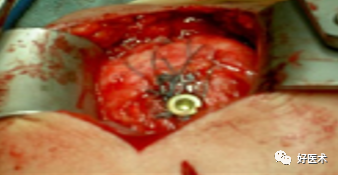

附:大结节撕脱骨折内固定

适用经手法复位失败,骨折移位超过1cm者;骨折块拉至肩峰下。

麻醉:颈丛麻醉 。

体位:仰卧位,患肩垫高与手术台成30°角。

操作方法:

切口:自肩峰外侧缘,约5cm,平行于三角纤维方向。

劈开三角肌纤维,切开三角肌肩峰和锁骨外侧端的附着点,显露结节部

在结节上用3.0钻头朝肱骨头方向钻孔,深约12-20mm

用钛丝穿过肩袖

将钛丝缠绕螺钉钉帽一圈

选择合适长度螺钉

拧入干预螺钉至钉帽外露3mm深度

用钢丝钳把钛丝缠绕拧紧,检查骨折复位情况

冲洗伤口,逐层缝合肌肉,皮肤切口

曲肘90°位三角巾悬吊制动,2周后开始被动活动